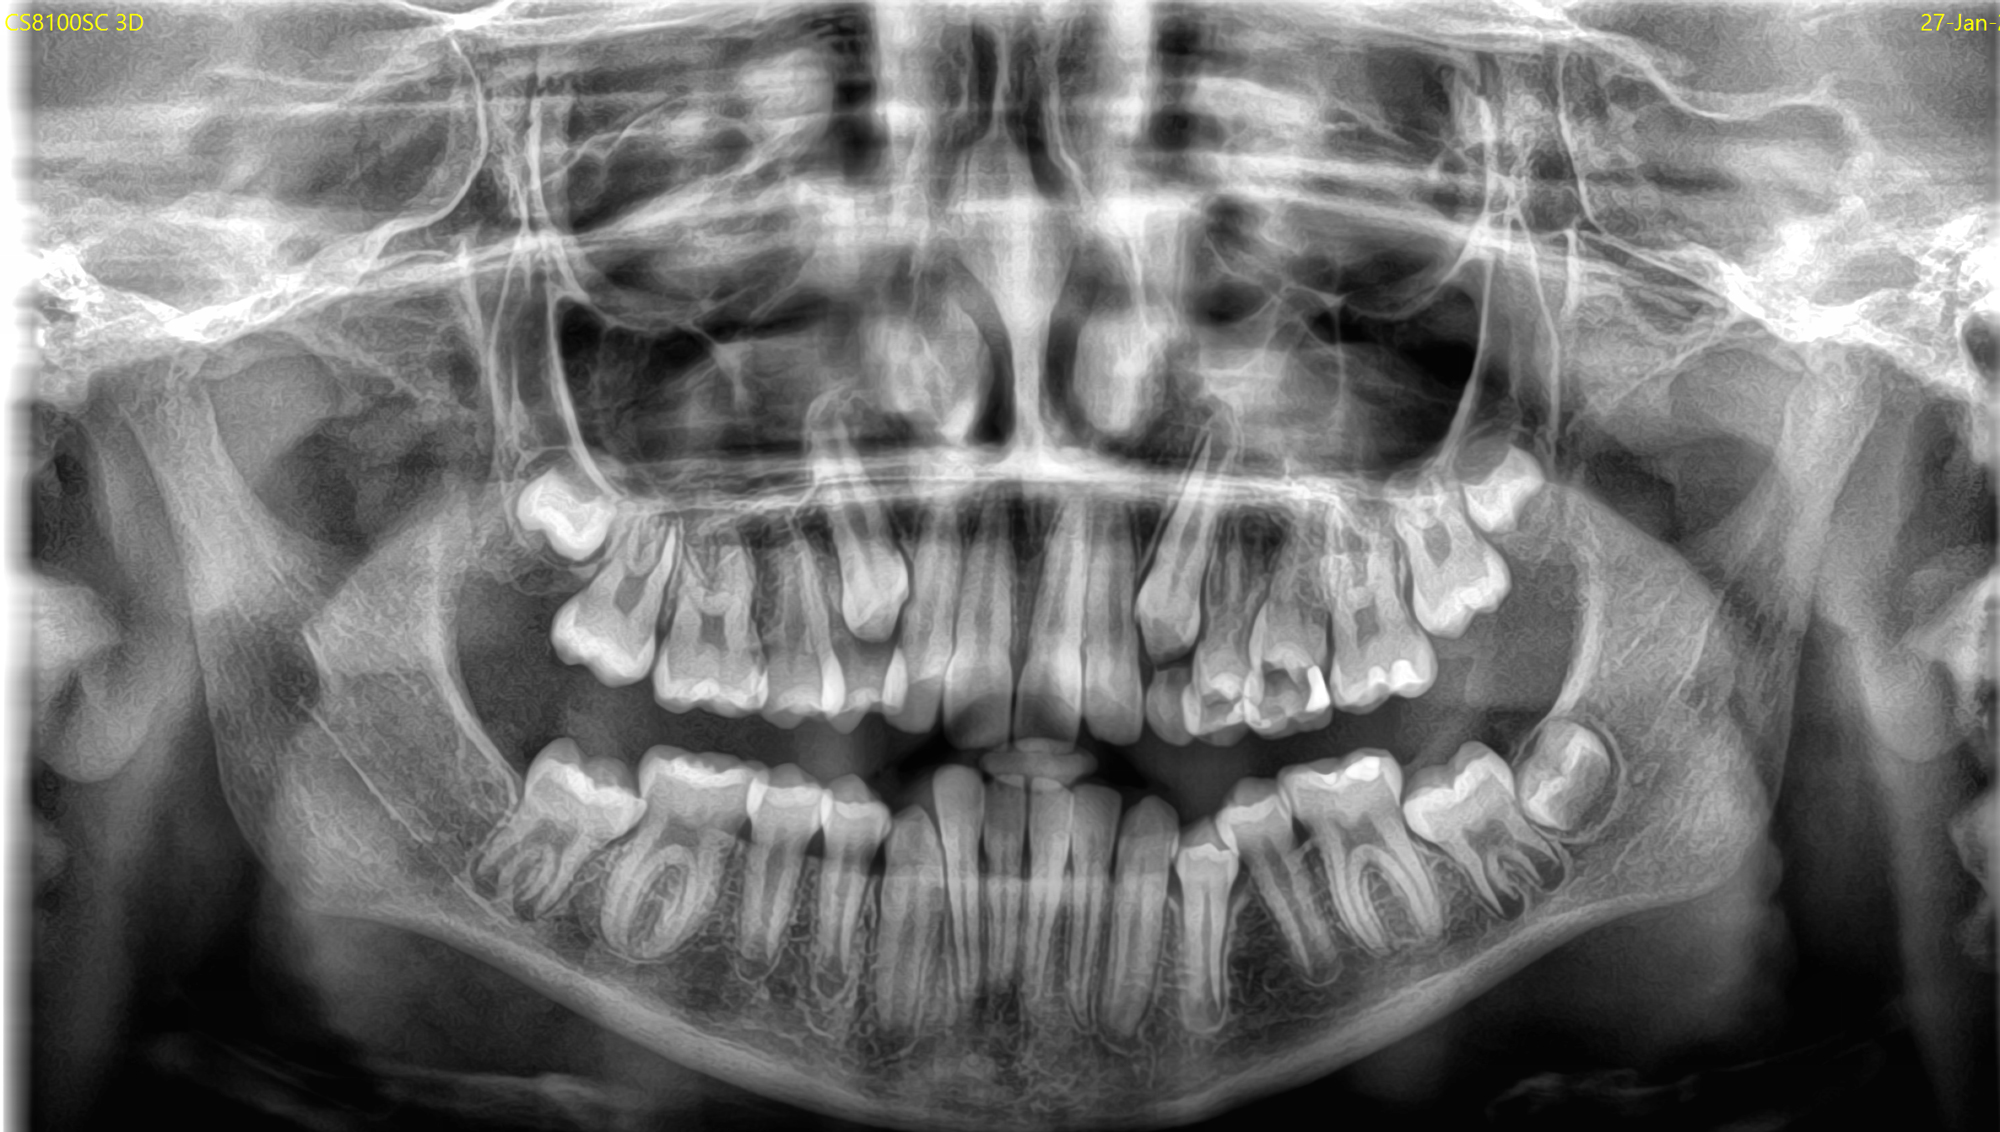

Το νέο μοντέλο CS 8200 3D Neo Edition της Carestream Dental συνδυάζει Ψηφιακή Πανοραμική με Ογκομετρικό Τομογράφο CBCT, με επιλογή εννέα οπτικών πεδίων και ανάλυση έως 75μm.

Το νέο αυτό μοντέλο αποτελεί την εξέλιξη του ιδιαίτερα πετυχημένου μοντέλου CS 8100 3D.

Με νέο εύχρηστο λογισμικό και ακόμα μεγαλύτερες δυνατότητες όπως το CS MAR, αλγόριθμος NAR, ανατομικά φίλτρα Endo, Perio,τεχνολογία Tomosharp, το καθιστούν ως το πιο κατάλληλο μηχάνημα για Οδοντιατρεία και Διαγνωστικά κέντρα καλύπτοντας όλο το φάσμα των απεικονίσεως οδοντογναθοπροσωπικής περιοχής με πεντακάθαρες εικόνες.